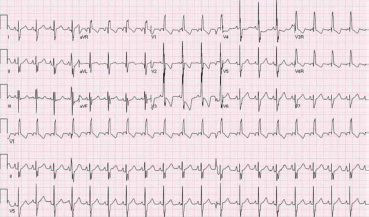

A figura a seguir é tipicamente encontrada em qual dos seguintes pós-operatórios?